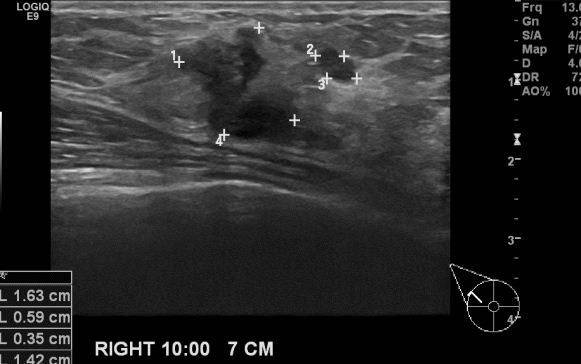

우측의 만져지는 멍우리와 통증으로 내원하신 40대 여성 분으로  우측 10시 방향에서

7cm 떨어진 거리의 만져지는 혹 조직검사 시행하여 우측 침윤성 유관암 진단 되었습니다.